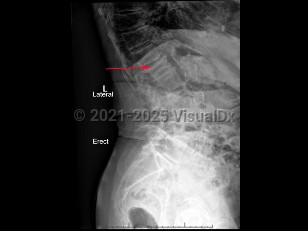

Classic history and presentation: OVCF can present with acute, localized spine pain that infrequently radiates to the ribs. Pain worsens with movement and palpation. However, two-thirds of OVCF are asymptomatic and found incidentally on lateral chest x-ray or with loss of the patient's height.

Grade / classification system: The Genant classification of vertebral fractures is based on morphology of the vertebral body (eg, wedge, biconcave, or crush deformities) and grades the severity of fracture.

- Grade 0 (normal): No vertebral height loss seen

- Grade 1 (mild fracture): 20%-25% vertebral height loss

- Grade 2 (moderate fracture): 25%-40% vertebral height loss

- Grade 3 (severe fracture): > 40% vertebral height loss